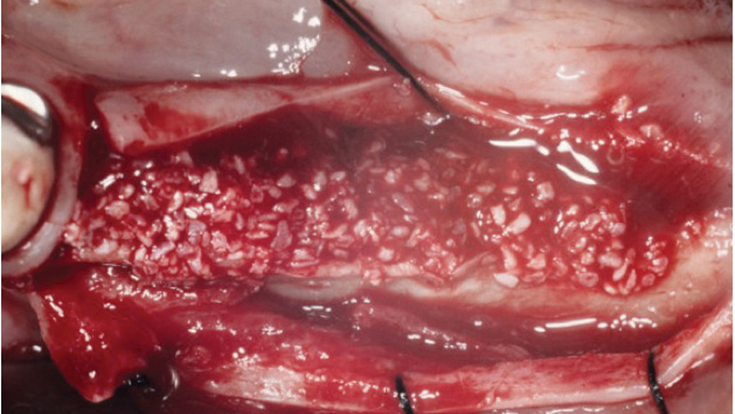

Clinical case: Ridge splitting technique using SmarThor + AnyRidge as expander

- Courtesy of Dr.Kwang-Bum Park, Korea -

Keywords

AnyRidge, ridge splitting, GBR, Dr. Kwang-Bum Park, mandibular posterior, SmartThor, Mega-Oss, thin ridge, bone regeneration

Products:

AnyRidge implant system. SmarThor, Mega-Oss